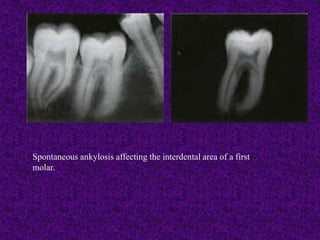

Infrapositioned maxillary central incisor initially

intruded at the age of 9.

A. Clinical photograph shows position of tooth

at age 13.

B. Radiograph shows extent of ankylosis-related

resorption. The pulp retained vitality, that is not

unusual in teeth with ankylosis-related resorption.